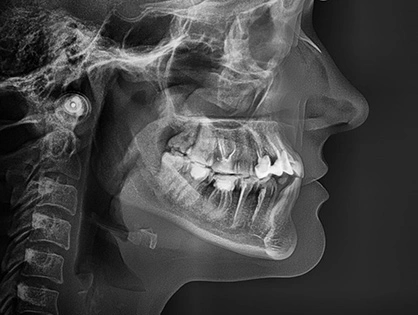

- Виявлення функціональних порушень та прогнозування проблем зубного ряду

- Діагностика захворювань скронево-нижньощелепного суглоба

Діагностика та стратегія лікування

Коректний план діагностики та лікування – важлива складова для вирішення таких проблем, як неправильний прикус, порушення жувальної функції і звичайно неестетичного вигляду зубів, незалежно від віку пацієнта.